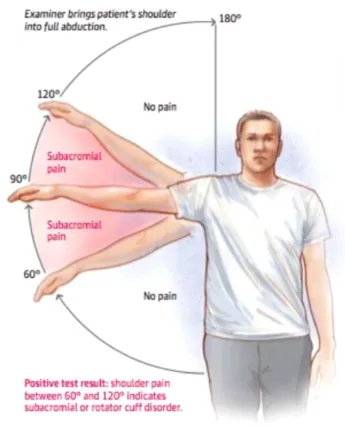

Najčešći simptomi smrznutog ramena razvijaju se postepeno i mogu trajati mjesecima:

stalna bol u ramenu koja se pojačava noću

ukočenost i smanjena pokretljivost

nemogućnost podizanja ruke iznad glave

poteškoće pri obavljanju svakodnevnih aktivnosti (odijevanje, češljanje, podizanje predmeta)

osjećaj slabosti u ramenu i ruci